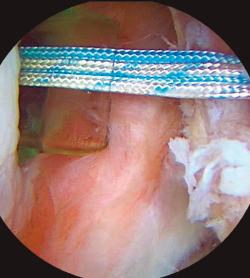

El desarrollo de la técnica de Latarjet y su adaptación a la artroscopia para la reconstrucción de las lesiones óseas en el hombro inestable parece haber relegado a un segundo plano la consideración de la lesión capsular y otras técnicas de tratamiento. A algunos cirujanos nos sigue sorprendiendo la indicación de un procedimiento de Latarjet para tratar pacientes sin grandes defectos óseos o con pérdida ósea combinada en ambos lados humeral y glenoideo, especialmente inferior a un 20% de la superficie de esta. La técnica artroscópica de remplissage (en la imagen, en un hombro izquierdo con visión superior y cánula en el portal a las 4:00) alcanza cada vez mayor número de cirujanos adeptos. Se constituye quizás como la opción más razonable para, asociada a la reparación de la lesión de Bankart, acometer el tratamiento de la inestabilidad anterior en pacientes con defectos óseos combinados en el lado glenoideo (≤ 20%) y en el humeral (independientemente de su tamaño).

La técnica artroscópica de remplissage (en la imagen, en un hombro izquierdo con visión superior y cánula en el portal a las 4:00) alcanza cada vez mayor número de cirujanos adeptos.